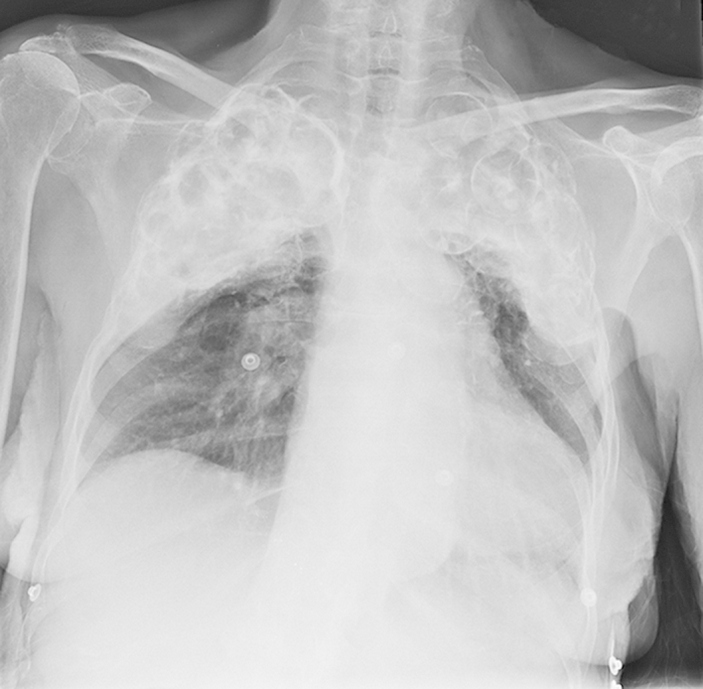

Перед вами КТ-сканограмма (см. CT localizer radiograph) задней поверхности грудной клетки 96-летней пациентки. В верхней части легких прекрасно заметны многочисленные округлые образования. Это шарики из люцита (также известного как оргстекло, акрил, полиметилметакрилат, плексиглас), которые указывают на то, что в молодости женщина болела туберкулезом.

С конца 1940-х по 1950-е годы для лечения стали использовать пломбаж. В верхней части грудной стенки хирургическим путем создавалась полость, и в образовавшееся пространство вводились разные инертные материалы: масло, собственный жир или фрагменты мышц пациента, парафин, резиновые шарики, люцитовые шарики и даже полиэтиленовые пакеты, заполненные полосками полиэтиленовой пленки — это также способствовало коллапсу легкого и ограничивало распространение инфекции на другие области легких.